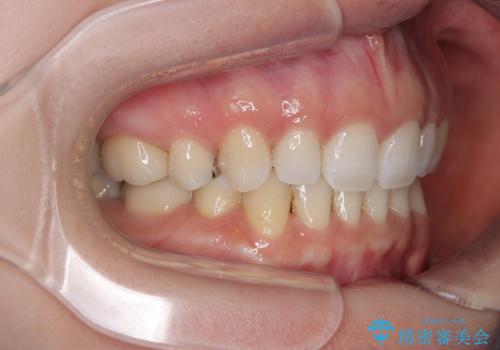

顎先に梅干し皺ができる 閉じにくい唇を抜歯矯正で閉じやすく

- 口元の突出感と口の閉じにくさを気にして来院された患者様です。

上下左右第一小臼歯4本を抜歯し、ワイヤー装置にて口元を引っ込めるよう矯正治療を行うこととしました。